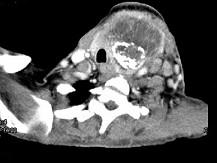

问题 女,64岁,发现双甲状腺肿大1月余,CT如图所示,最可能诊断为()

选项 A.结节性甲状腺肿 B.甲状腺腺瘤 C.甲状腺癌并淋巴结转移 D.甲状腺转移瘤 E.甲状腺结核

答案 C